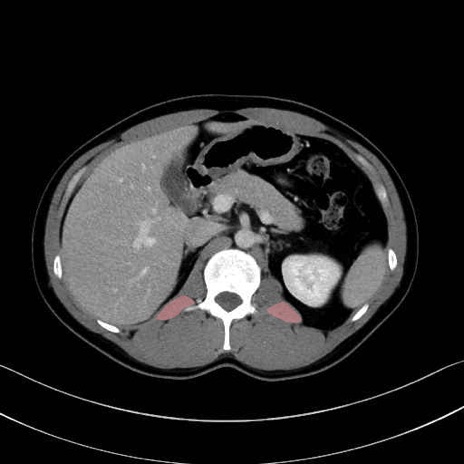

腰方形筋 (Quadratus lumborum)

広背筋 (Latissimus dorsi)

脊柱起立筋 (Erector spinae)

多裂筋 (Multifidus)